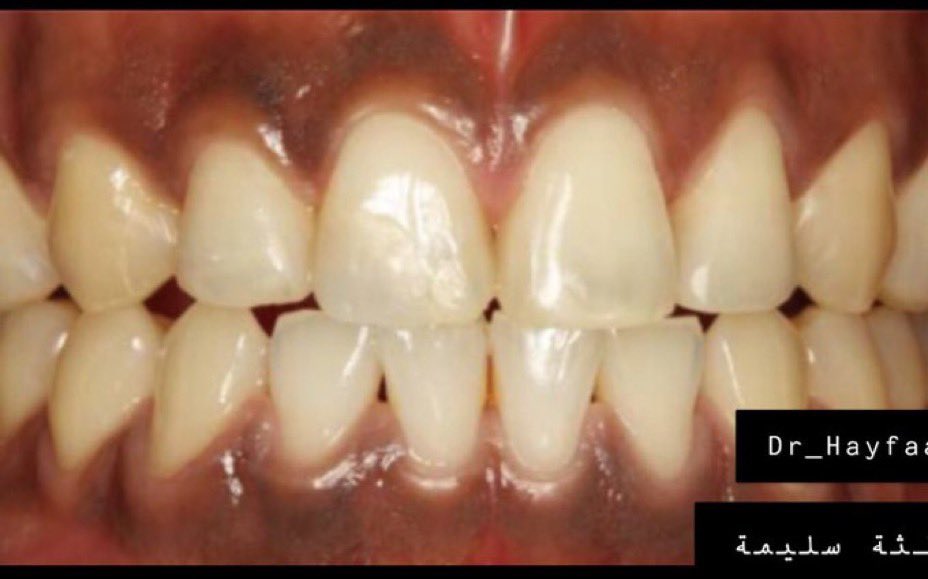

اللثة السليمة:

لمعرفة اللثة المريضة يجب أولا معرفة السليمة ونعرف الاختلافات البسيطة بين جميع الأعراق.اللثة السليمة لونها زهري (غالبا)ملتصقة بالأسنان لامعة(غالبا)لا تنزف عند اللمس أوالتفريش أو بدون سبب/بعض البشرلديهم تصبغات سمراء طبيعية #صحة_أسنانك